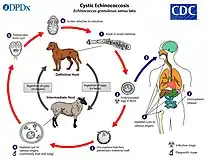

Echinococcosis

The rates of echinococcosis is higher in rural areas, and there are more than one million people infected currently.[33] Untreated alveolar echinococcosis is fatal.[34] It is caused by ingesting parasites in animal feces.[35] There are two versions of the disease: cystic and alveolar. Both versions involve an asymptomatic incubation period of several years. In the cystic version, liver cysts cause abdominal pain, nausea and vomiting while cysts in the lungs cause chronic cough, chest pain, and shortness of breath. In alveolar echinococcosis, a primary cyst develops, usually in the liver, in addition to weight loss, abdominal pain, general feeling of ill health, and signs of liver failure.[34]

Surgery and drugs can both be used to treat echinococcosis.[34] It can be prevented by deworming dogs, sanitation, proper disposal of animal feces, health education, and livestock vaccination.[36] Cystic echinococcosis is found in the eastern portion of the Mediterranean region, northern Africa, southern and eastern Europe, the southern portion of South America, and central Asia. Alveolar echinococcosis is found in western and northern China, Russia, Europe, and northern North America.[35] It can be diagnosed through imaging techniques and serological tests.[36]